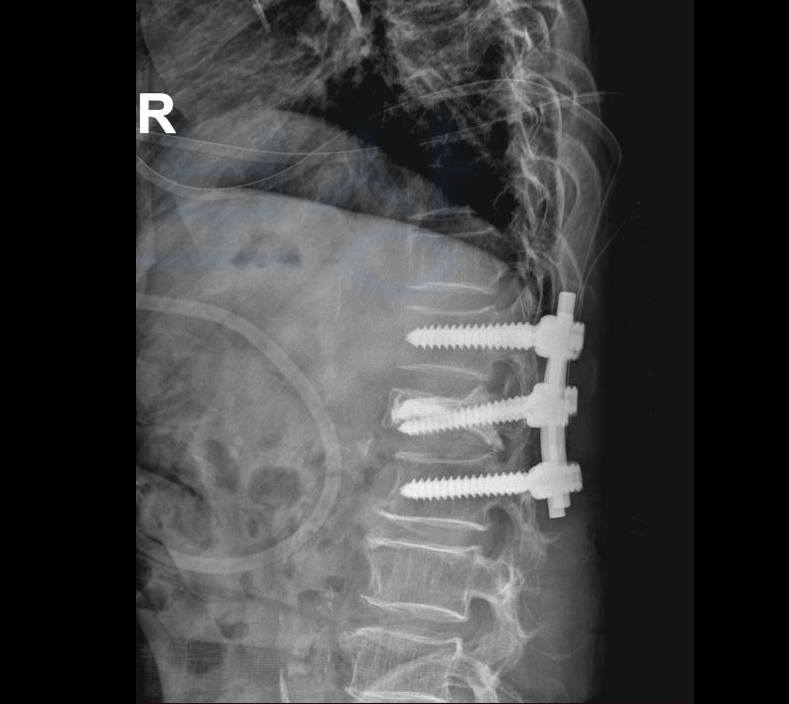

사고 이후 최@@님은 극심한 허리 통증을 호소하셨고 병원에 내원하여 정밀검사를 한 결과

요추1번골절 S32020 진단받아 허리 보호대 (TLSO보조기) 착용하며 요양하셔야 했는데요, 문제는 골절된 척추체가 시간이 경과하며 찌그러지듯 심하게 주저앉게 되었고 결국척추체의 공간을 확보한 후 의료용 시멘트를 주입하여 굳히는 골시멘트술을 받으셔야 했습니다.

하지만 시간이 결과함에도 요추1번골절 호전이 안되었고 결국 척추유합술 까지 받게 되었죠.